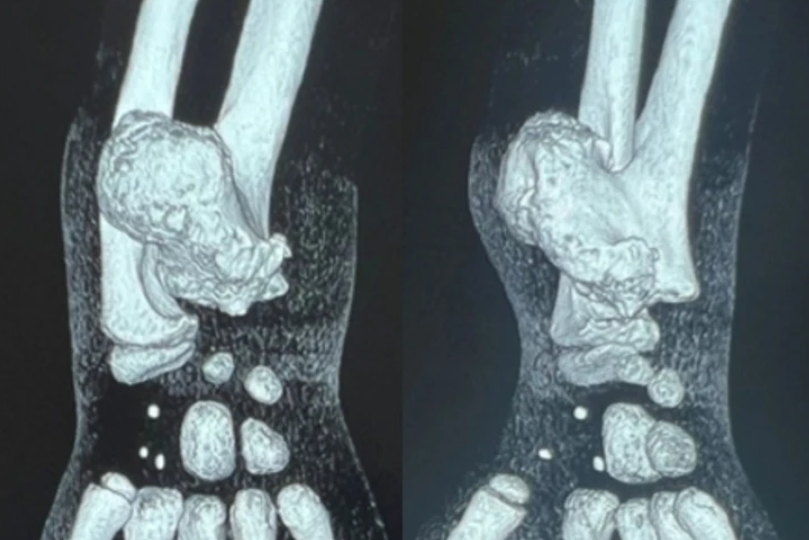

Осенью 2025 года семья обратилась за помощью в НИИТО. Врачи диагностировали остеохондрому – доброкачественное, но агрессивно растущее костно-хрящевое образование размером 4×5 см. Оно угрожало деформацией кости и сдавливало нервные окончания.

Новообразование располагалось вблизи локтевой артерии и локтевого нерва. Необходимо было действовать максимально аккуратно, –объясняет врач-ортопед Дастанбек Абдикапаров.

Хирурги удалили опухоль, не задев критически важные сосуды и нервы. Движения в запястье не нарушены. После того, как швы заживут, ребёнок начнёт программу восстановления – курс плавания и разработки руки.

Фото: пресс-служба Новосибирского НИИТО им Я.Л. Цивьяна